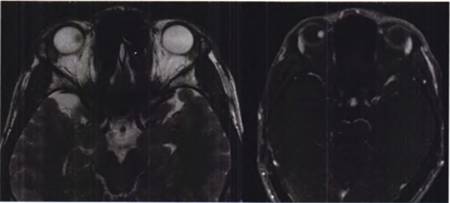

入院后行彩色多普勒超声检查示右眼视鼻上方突向玻璃体实性半球形病变,基底直径8.4 mm,高度4.4 mm,边界清晰,内回声尚均匀,彩色多普勒血流成像可探及较丰富血流信号,玻璃体可探及弱点状回声及带状回声与其相连,彩色多普勒血流成像可见血流信号,考虑右眼球内实性占位病变;右眼玻璃体混浊;右眼继发性视网膜脱离(图2)。

图2 右眼视力下降患者右眼彩色多普勒超声图像,图中+示肿瘤边界,数字示肿瘤径线测量标识

UBM示双眼前段未见明显异常。MRI示右眼内上壁异常信号,呈等T1、等T2信号影,增强未见明显强化(图4)。

图4 右眼视力下降患者右眼眶MRl险查结果